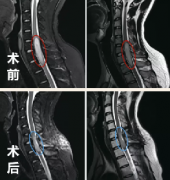

脊髓髓内肿瘤相对少见,占全部中枢神经系统肿瘤的5%-10%,大约55%的儿童硬膜下肿瘤位于髓内...

脊髓髓内肿瘤手术失败因素分析,同髓外肿瘤一样,髓内肿瘤也有三种较常见的病理类型,分别为室管膜瘤(30%-40%)、星形细胞瘤(30%-35%)和血管母细胞瘤(2%-15%),共占全部髓内肿瘤...

同髓外肿瘤一样,髓内肿瘤也有三种较常见的病理类型,分别为室管膜瘤(30%-40%)、星形细胞瘤(30%-35%)和血管母细胞瘤(2%-15%),共占全部髓内肿瘤的90%以上。一般可逆的及细微的电...